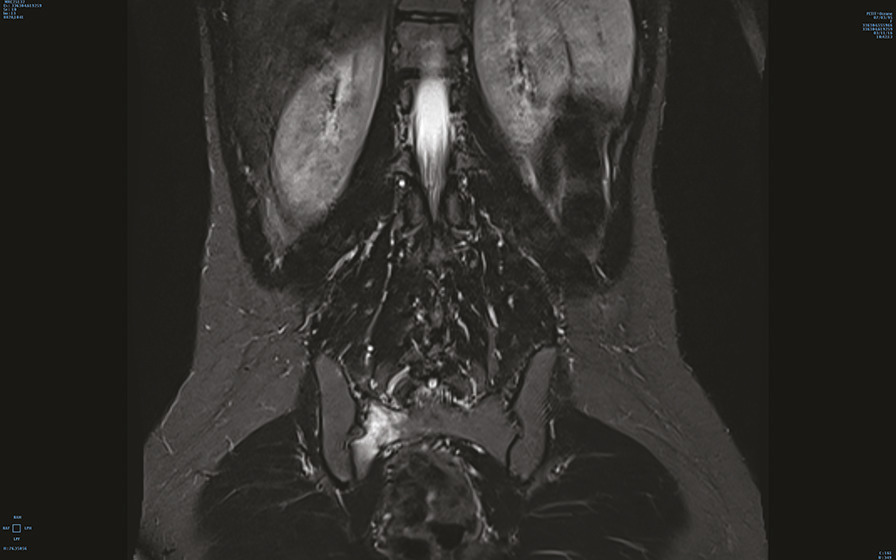

Engagée depuis 2 mois, cette jeune militaire consultait pour des paresthésies des orteils, sans notion de traumatisme aigu. Sédentaire auparavant, elle n’avait aucun antécédent particulier. Son indice de masse corporelle était de 20 kg/m2. L’examen notait une douleur neurogène avec trouble des sensibilités prédominant à l’extrémité du pied droit, sans syndrome radiculaire ni rachidien, d’horaire non mécanique. Le test de Faber était positif. Réalisée en seconde intention, l’IRM du bassin (v. figures) montrait une fracture de contrainte de l’aileron sacré droit. Le bilan biologique était sans particularité. Une cure courte d’anti-inflammatoires non stéroïdiens et la limitation au minimum des activités physiques entraînaient la guérison en 8 semaines.